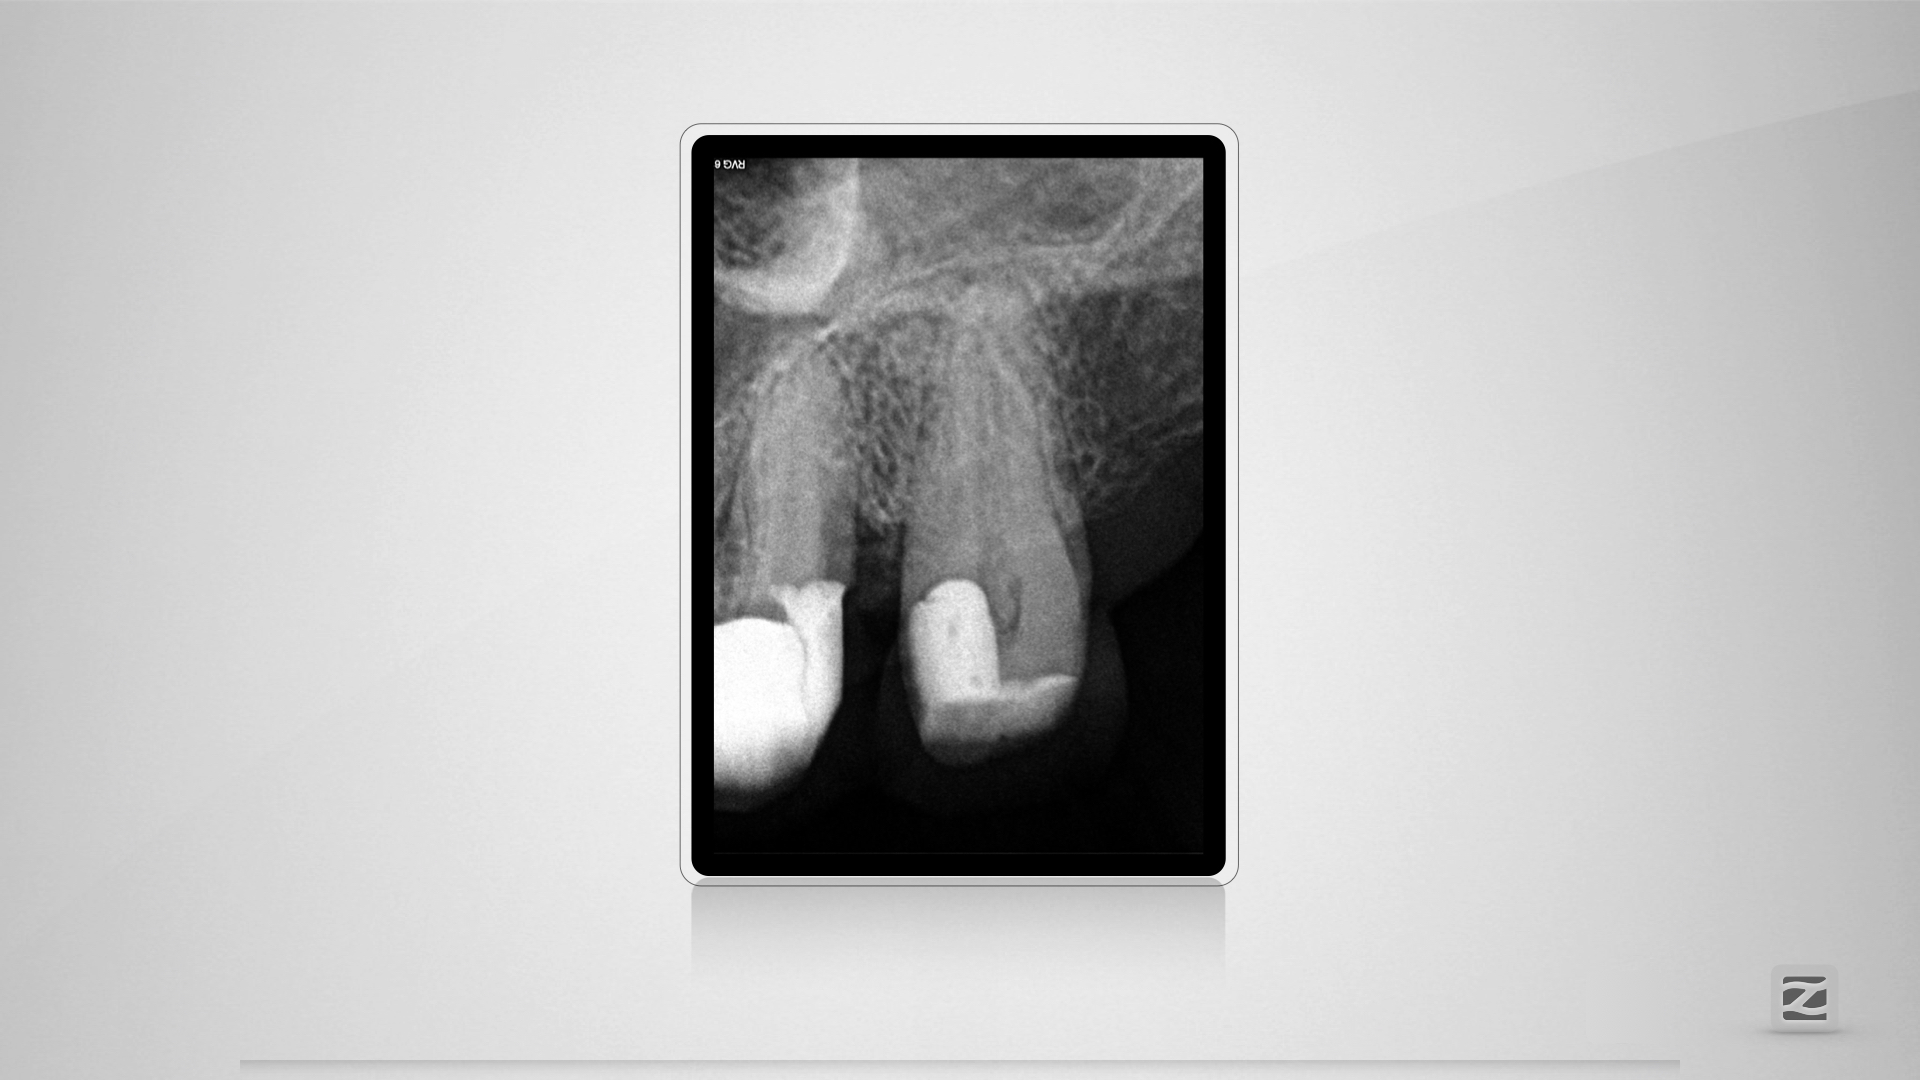

27D.001

Großer Dentikel, tiefer Split.